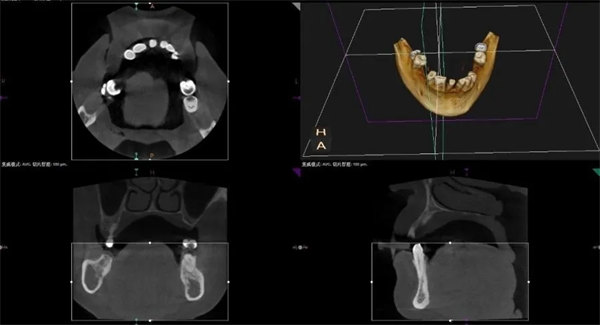

午休時間,李偉主任帶領科室團隊為患者行舌異物取出術,順利取出了數月來困擾患者生活的牙齒殘片。口腔科團隊精湛的醫術,高尚的醫德醫風,得到了患者和家屬的認可。

術后CBCT檢查